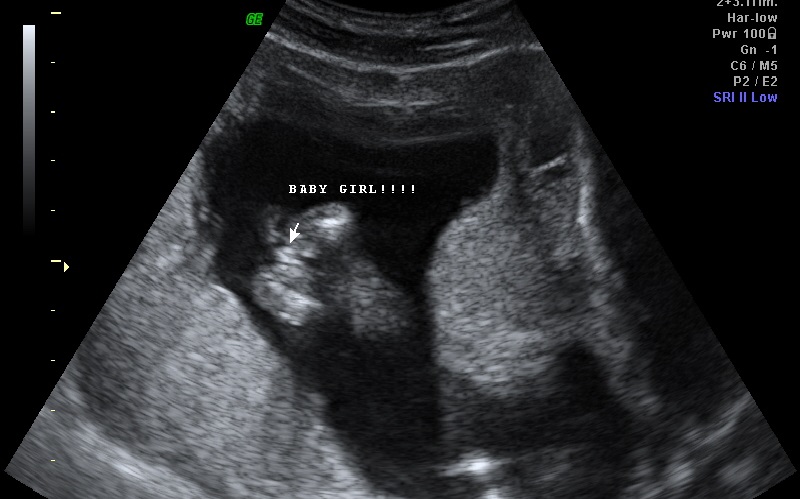

hello everyone :) this was taken at 14wks 6days at our 2d/3d gender scan U/S we already have a 19 month boy and i just want a 2nd opinion from another U/S tech please help thank youAttachment 12397Attachment 12398